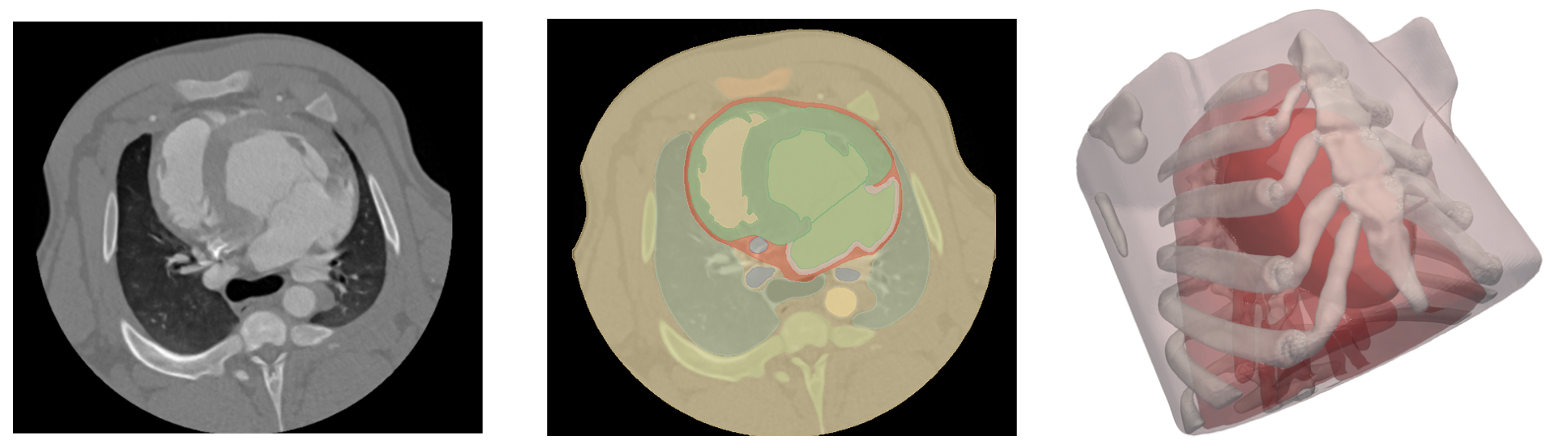

Medical imaging provides the foundation for modern diagnosis and therapy planning. In this project, we will explore how geometries of organs or tissues can be reconstructed from medical images such as MRI or CT scans. Using mathematical modeling and computer-based methods, we will learn how to transform image data into digital models that can be used to simulate medical treatments — for example, blood flow in vessels or the delivery of medication. Special emphasis will be placed on the interpretation of the simulation results, helping us understand how modeling can support real medical decisions. Students will use open-source software for the generation of digital geometries from real medical data, and will apply linear algebra and numerical methods to connect with virtual simulations. Prior knowledge is welcome, but not required.